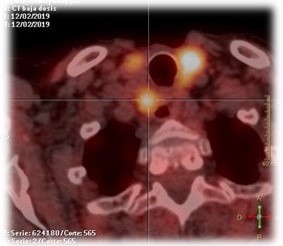

The patient remained disease-free for ten years until new symptoms and biochemical abnormalities reappeared (PTH 229.2 pg/mL, calcium 11.7 mg/dL). Cervical CT and 18F-choline PET-CT identified a hypermetabolic paraesophageal lesion (SUVmax 2.8, 6×7 mm) and three nodules in the upper right thyroid lobe (Figure 1).

Figure 1: (A) Ultrasound: pathological parathyroid gland ultrasound. (B) PET-CT with 18F-Choline: hyperactive parathyroid gland.